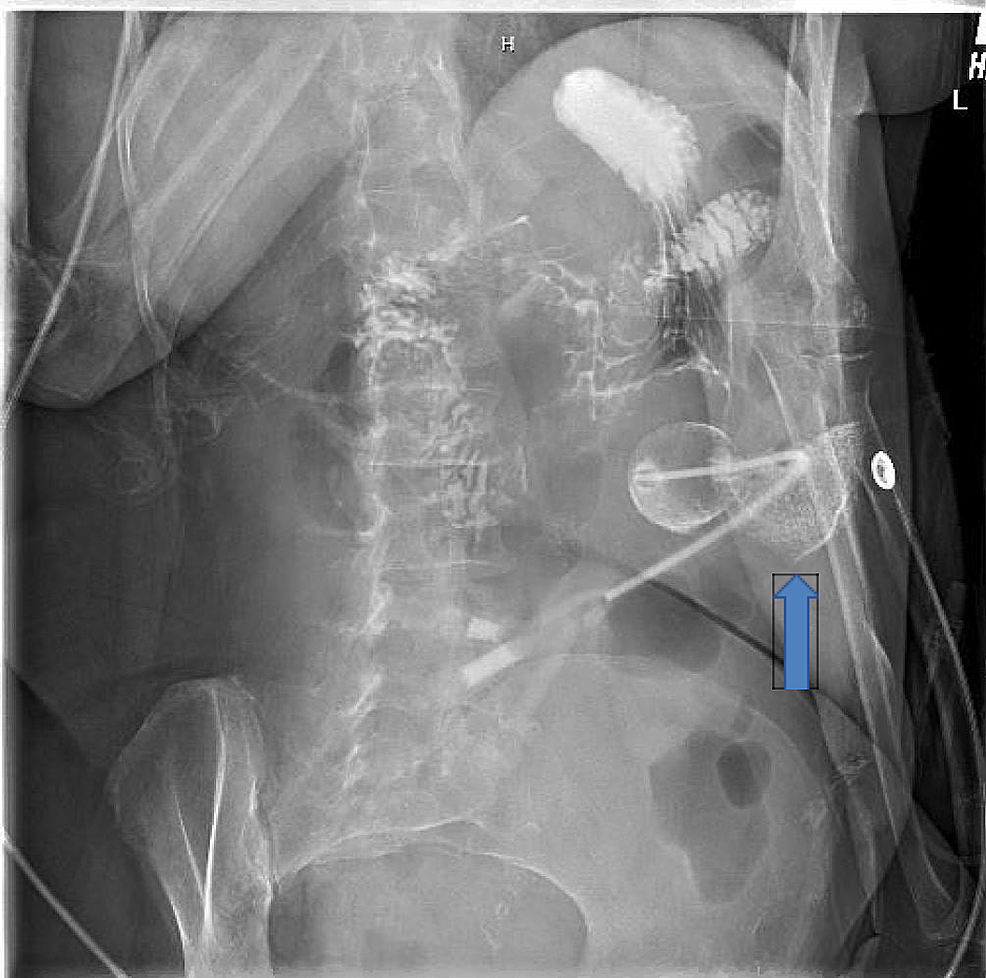

Abdominal radiograph showing appropriate placement of feeding tube

Abdominal radiograph demonstrates gastrostomy tube and Openi G-Tube Placement Check X Ray Describe the anatomy of gastrostomy tube placement. Gastrostomy tubes may be placed endoscopically, surgically, or radiologically. Descend in the midline, following the path of the esophagus and avoiding the contours of the. Classically, confirmation is achieved by. Turn the patient to right lateral decubitus (preferred) or right posterior oblique positions if the patient can tolerate and assistance for. A correctly. G-Tube Placement Check X Ray.